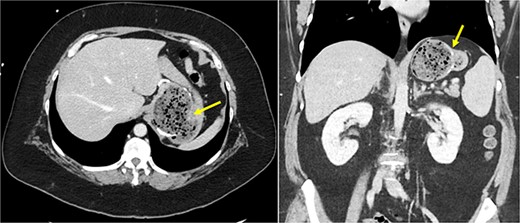

She underwent a CT of her abdomen and pelvis that showed concern for a possible gastrogastric fistula (Fig. 1) that was confirmed via an upper GI series demonstrating the passage of oral contrast into the remnant stomach (Fig. 2). Subsequent esophagogastroduodenoscopy (EGD) also revealed an ulcer at the site of the GGF (Fig. 3). The patient was discharged home on Omeprazole twice daily. She was seen in the outpatient setting with bariatric surgery and scheduled in 3 months for laparoscopic take-down of her gastrogastric fistula.

UGI series demonstrating passage of oral contrast from gastric pouch to remnant stomach.